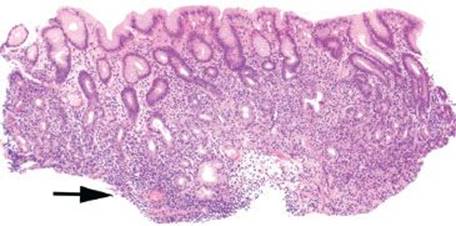

Figure 2.97 Chronic gastritis pattern, basal lymphocytic infiltrate subpattern, early AMAG. The dominant pattern of injury in this tissue fragment is a low-lying lymphocytic infiltrate that hugs the muscularis mucosae and expands the lamina propria below the base of the glands (arrow). The oxyntic glands (bracket) indicate that the compartment of injury is body/fundus. Further investigation reveals an area of oxyntic gland atrophy (arrowheads), suggesting early AMAG.